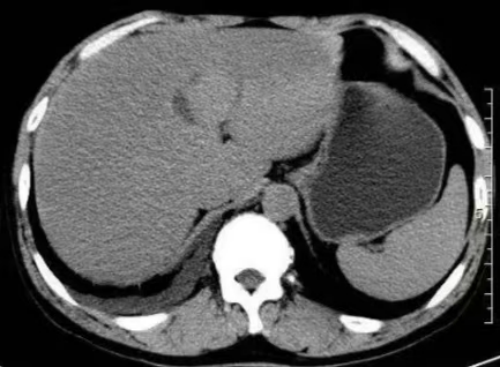

(图3)脂肪肝CT表现

如何检测脂肪肝呢?通常,通过影像学检查,如超声、CT或MRI,可以直观地评估肝脏的脂肪量。此外,血液检查能够帮助判断肝功能和脂类代谢的情况,而在某些情况下,肝穿刺活检可以提供更为详细的肝脏病理信息。针对脂肪肝的治疗,首先要调整生活方式。均衡饮食、增加体育锻炼是最重要的两项措施。研究表明,减轻体重5%至10%即可显著改善肝脏健康。患有肥胖、糖尿病等相关疾病的人,更需监听医生建议,制定个性化的健康管理方案。